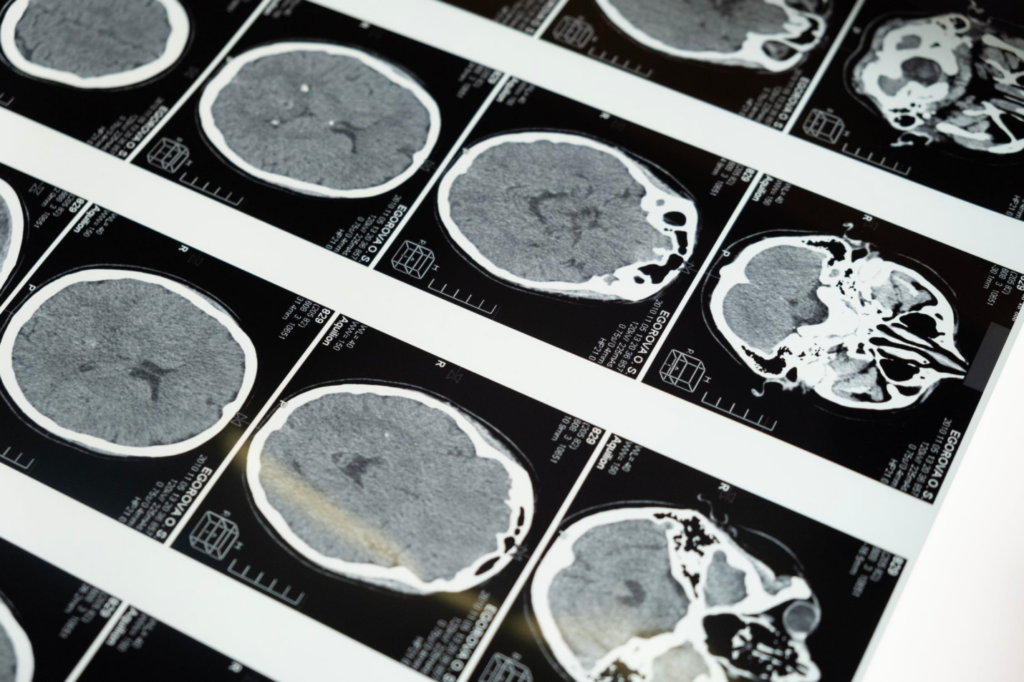

Neuroimaging Three important brain imaging techniques ScIU